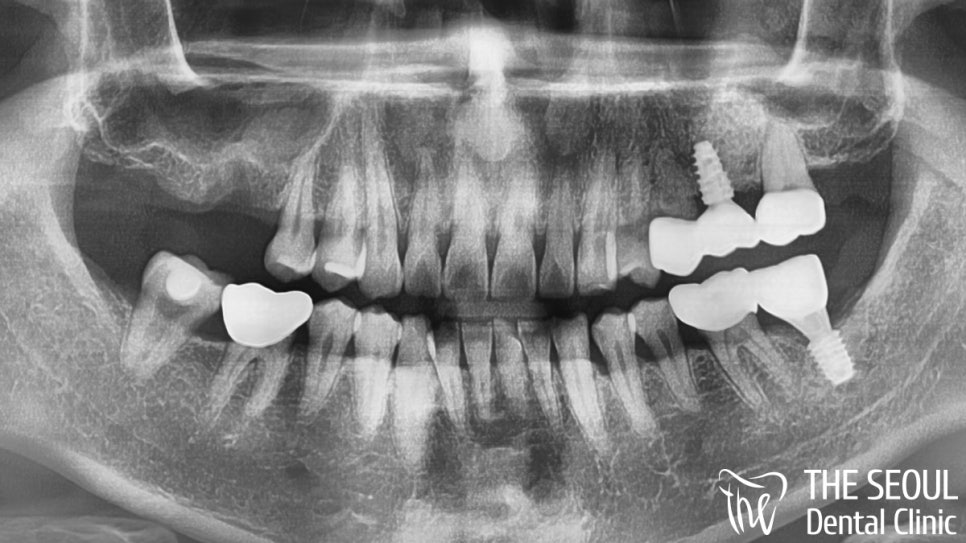

또한 옆에 있는 17번 치아도 이미 상실되어 있었기에

두 곳에 식립을 진행하는 것으로

최종적인 방향을 잡았습니다.

이분의 파노라마를 자세히 살펴보면

이러면 정말 곤란한데 말이죠..

문제는 여기서 끝이 아니었는데요.

약간의 상악동 염증도 함께 발견되었기 때문에

예상했던 것보다 훨씬 더 까다롭고

복잡한 과정이 되겠다는 판단이 들었습니다.

그래도 최선을 다해 진료를 도와드려야겠군요!!

정해진 곳에 가이드 임플란트 식립을 마쳤습니다!

정말 깔끔하게 자리를 잡고 있는

픽스쳐를 볼 수 있는데요.

이후 골융합과 회복을 확인한 뒤에

최종 보철을 올려드리며

마무리를 도와드리기로 했습니다.